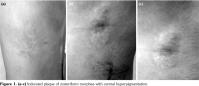

An 18-year-old healthy, male patient presented with complaints of hardness and discoloration of the skin at the right posteroinferior side of his trunk with a zosteriform distribution of T10-12 dermatomes, over a period of two years. We detected no characteristic finding in his medical/family history and physical examination except indurated plaque that measured 9x6 cm in diameter with central hyperpigmentation among the xyphoid and umbilicus that extended to the lateral part of the trunk with atrophic lesions in a zosteriform distribution (Figure 1). We detected no history of herpes zoster or other skin lesions on the site of ZM, abnormal skin moisture, suggestive signs of other extracutaneous, musculoskeletal or systemic sclerosis. Serology for varicella-zoster